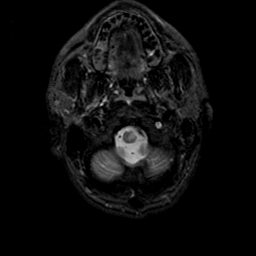

MR Study #23, January 26, 1992 -- Slice #3

[Home][Help][Clinical][Tour 1][Tour 2] Slice 3